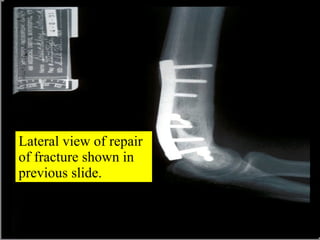

Lateral view of repair of fracture shown in previous slide.

Lateral view ofrepair of fracture shown in previous slide.